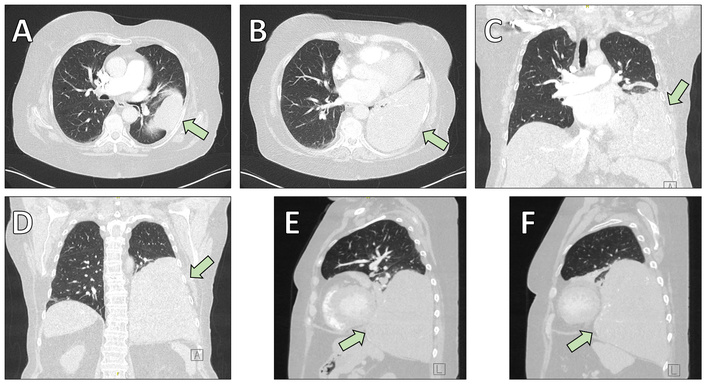

A 69-year-old woman with a history of pustular psoriasis on long-term corticosteroid therapy and a 20-pack-year smoking history presented with progressive exertional dyspnea. An SFT of the left lower lobe had been diagnosed by computed tomography (CT)-guided biopsy four years earlier, but surgery was initially deferred. Follow-up imaging showed marked tumor growth to approximately 15 × 14.5 × 12.5 cm (Figure 1, Figure 2A), leading the multidisciplinary tumor board to recommend resection.

Preoperative chest computed tomography (CT) illustrating the anatomical localization of the solitary fibrous tumor (arrows). (A, B) Axial (transversal) images demonstrating the mass infiltrating the lung parenchyma of the left lower lobe. (C, D) Coronal reconstructions highlighting the cranio-caudal extension of the lesion. (E, F) Sagittal reconstructions further delineate tumor size and spatial relationship to adjacent thoracic structures.